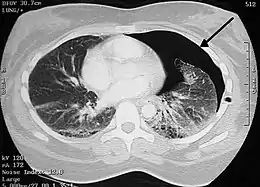

Computed tomography

A CT scan is not necessary for the diagnosis of pneumothorax, but it can be useful in particular situations. In some lung diseases, especially emphysema, it is possible for abnormal lung areas such as bullae (large air-filled sacs) to have the same appearance as a pneumothorax on chest X-ray, and it may not be safe to apply any treatment before the distinction is made and before the exact location and size of the pneumothorax is determined.[15] In trauma, where it may not be possible to perform an upright film, chest radiography may miss up to a third of pneumothoraces, while CT remains very sensitive.[18]

A further use of CT is in the identification of underlying lung lesions. In presumed primary pneumothorax, it may help to identify blebs or cystic lesions (in anticipation of treatment, see below), and in secondary pneumothorax, it can help to identify most of the causes listed above.[15][19]